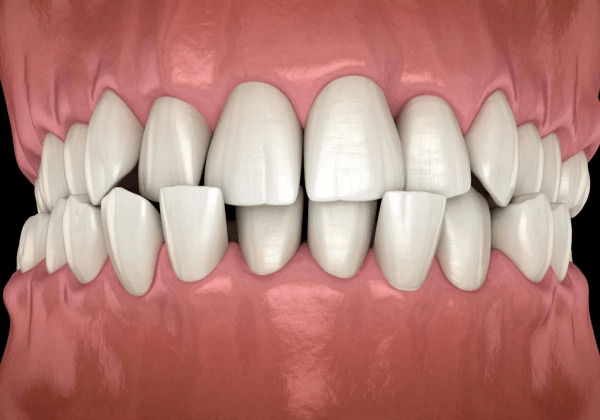

Khớp cắn chéo là tình trạng các răng cửa hoặc răng hàm không căn chỉnh đúng vị trí khi cắn chặt hai hàm. Thay vì các răng hàm trên phủ lên các răng hàm dưới một cách phù hợp, chúng lại bị lệch hoặc chéo sang bên trong hoặc bên ngoài, gây mất thẩm mỹ, khó khăn trong việc ăn nhai và các vấn đề khác về sức khỏe răng miệng.

Các loại khớp cắn chéo thường gặp

Khớp cắn chéo răng trước

Đây là tình trạng răng cửa trên hoặc dưới bị lệch hoặc chéo sang phía trong khi cắn. Đặc trưng của loại này là ảnh hưởng lớn đến thẩm mỹ và khả năng phát âm.

Khớp cắn chéo răng sau

Răng hàm trên hoặc dưới không phát triển đúng cách, gây lệch phía trong hoặc phía ngoài, thường liên quan đến xương hàm hoặc do mọc răng sai vị trí.

Khớp cắn chéo một bên

Chỉ gây lệch hoặc chéo khớp cắn ở một bên của hàm, thường do răng mọc sai hoặc sự phát triển không đều của hàm.

Khớp cắn chéo hai bên

Lệch hai bên của hàm, ảnh hưởng toàn diện đến chức năng nhai, phát âm và thẩm mỹ.